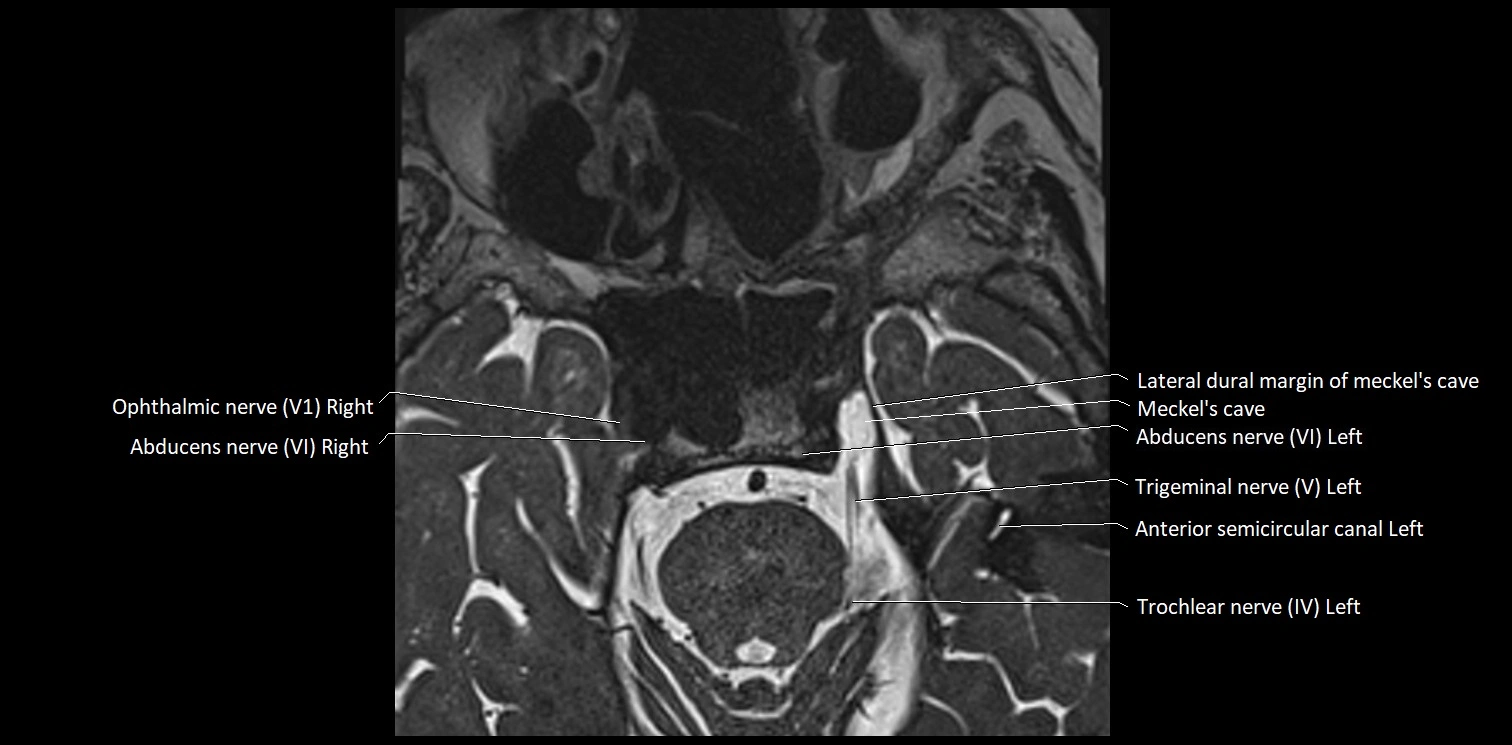

MRI Appearance

• The abducens nerve is a small, thin, linear structure

• Best visualized on high-resolution T2-weighted 3D MRI sequences (e.g., FIESTA or CISS)

• Seen as a hypointense (dark) line running from the brainstem at the pontomedullary junction, traversing the prepontine cistern, and entering Dorello’s canal under the petrosphenoidal ligament, then into the cavernous sinus, and finally the orbit

• May be challenging to visualize in standard MRI due to its small size

• Pathology may be inferred by absence, displacement, or enhancement of the nerve

MRI images

image